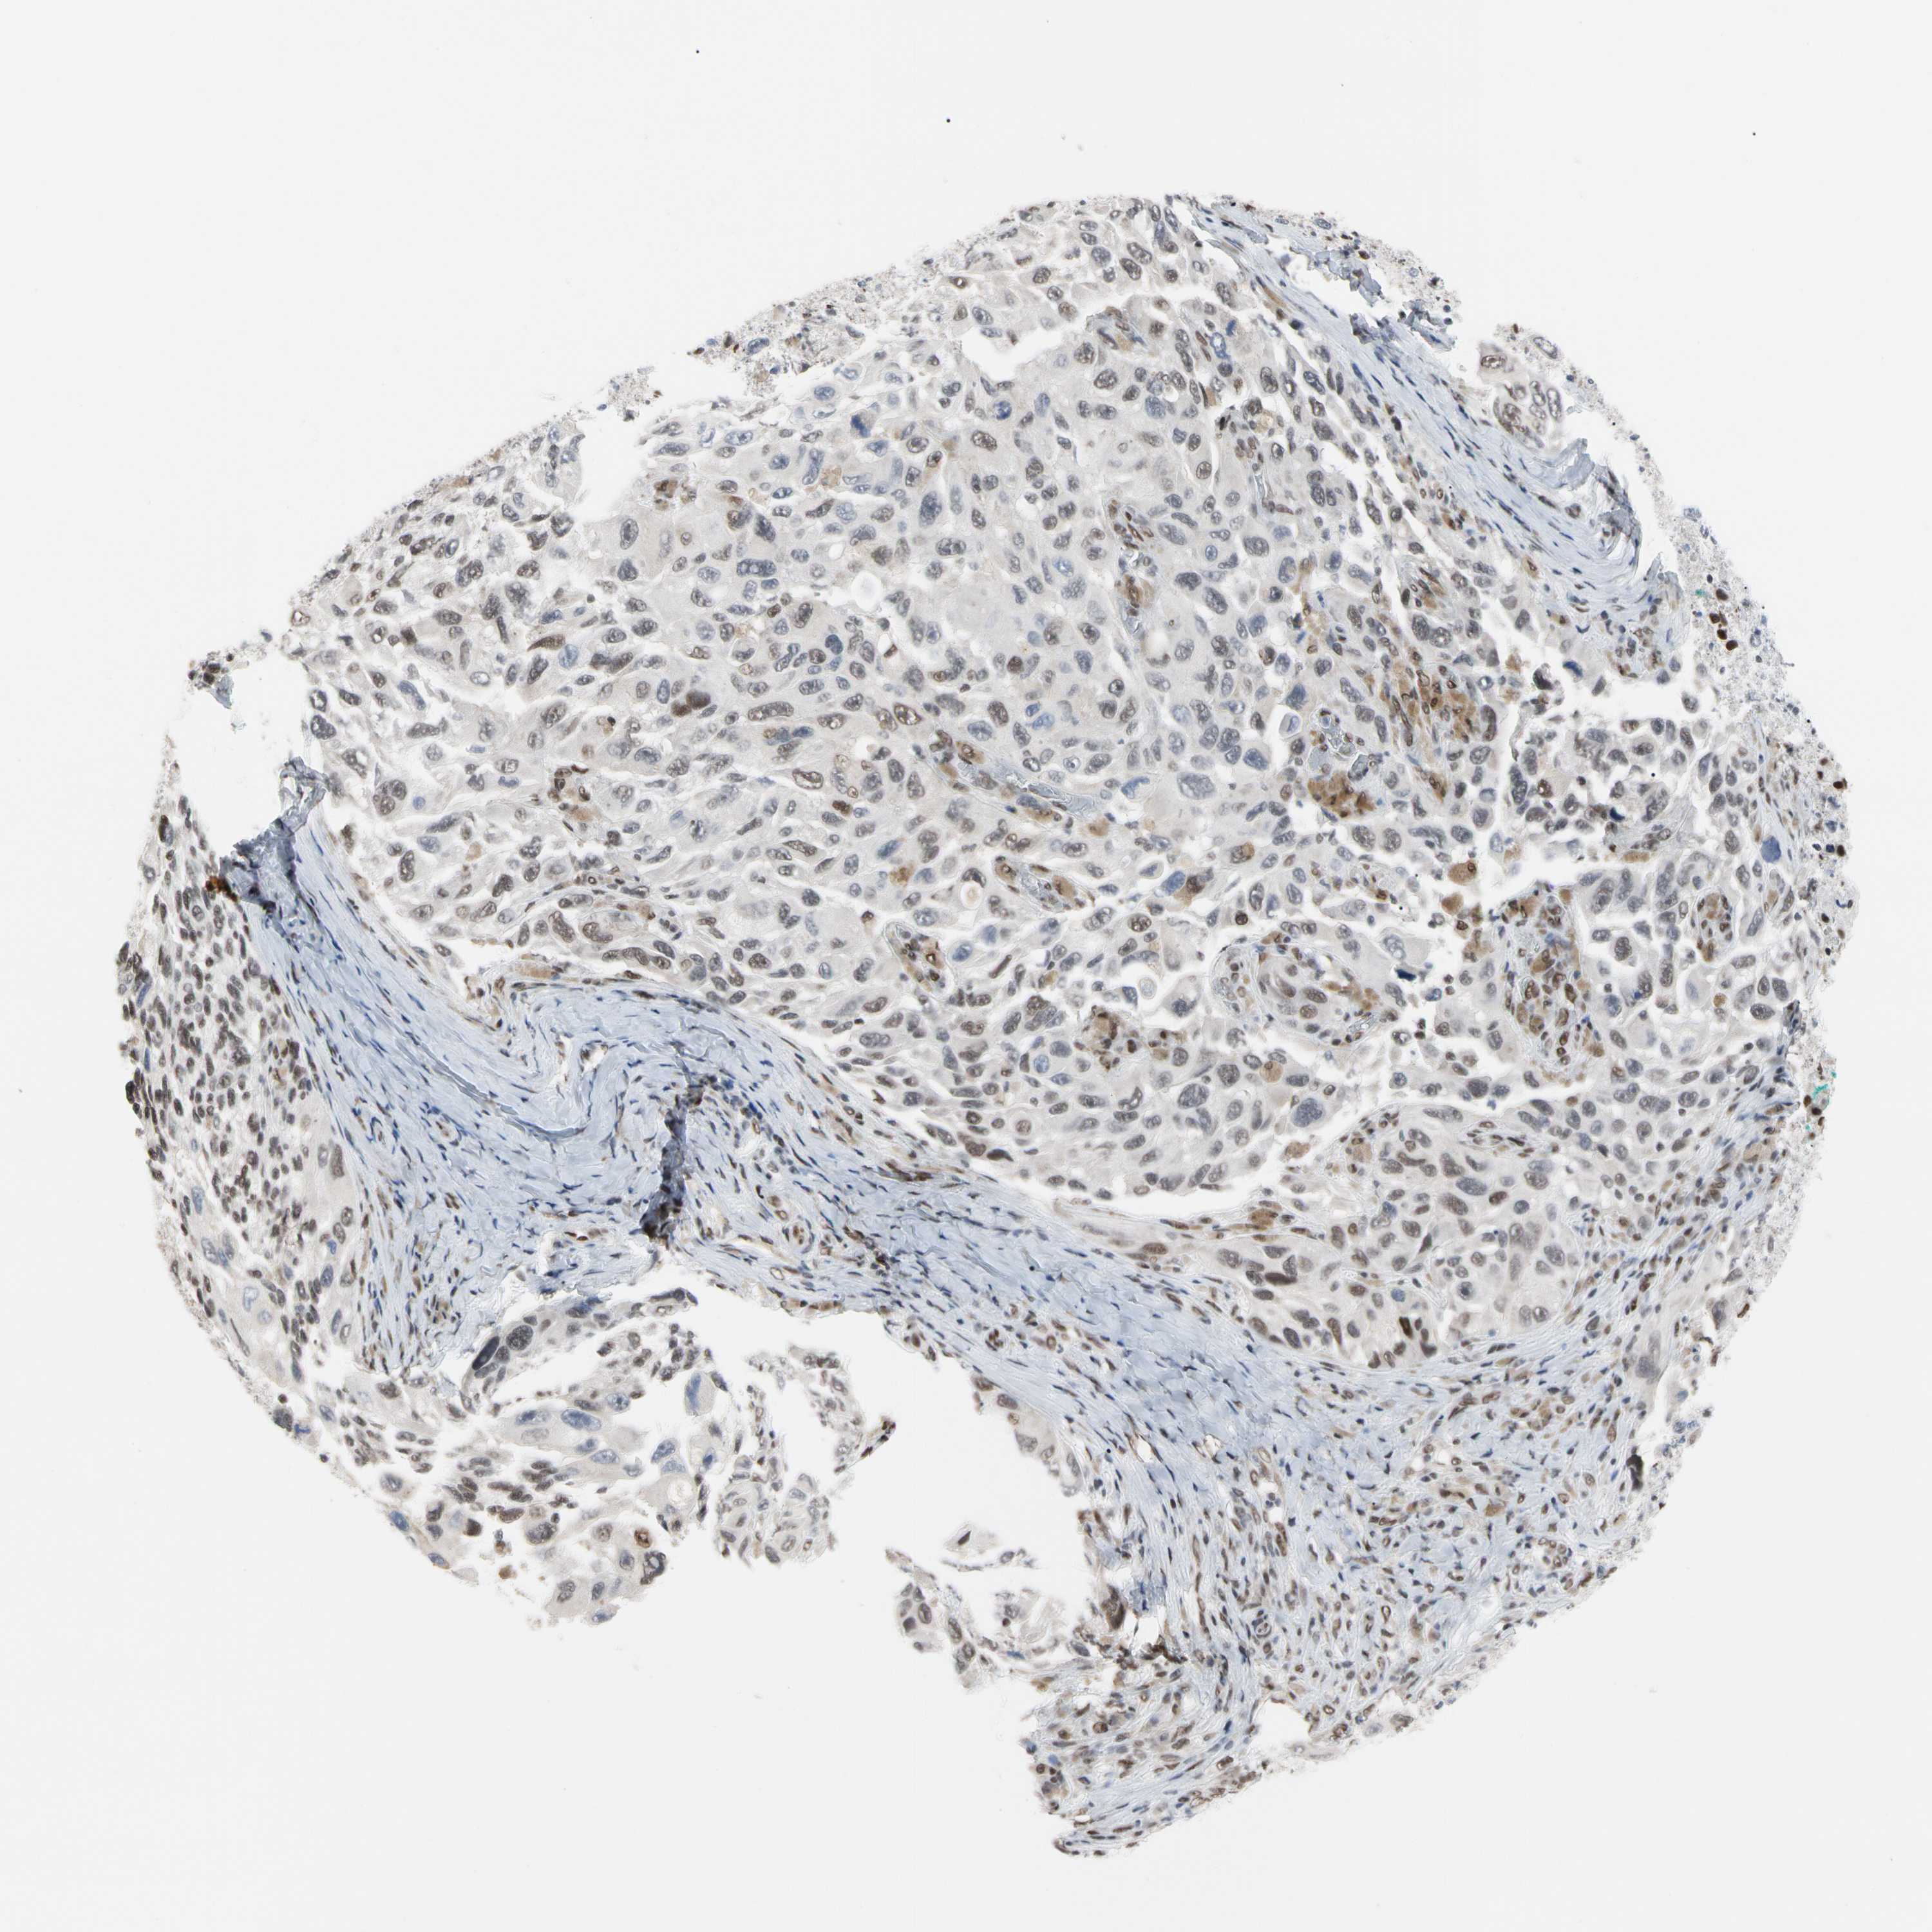

MELANOMA - Protein expressioni

A mouse-over function shows sample information and annotation data. Click on an image to view it in a full screen mode. Samples can be filtered based on level of antibody staining by selecting one or several of the following categories: high, medium, low and not detected. The assay and annotation is described here.

Note that samples used for immunohistochemistry by the Human Protein Atlas do not correspond to samples in the TCGA dataset.

Antibody stainingi

Antibody staining in the annotated cell types in the current human tissue is reported as not detected, low, medium, or high, based on conventional immunohistochemistry profiling in selected tissues. This score is based on the combination of the staining intensity and fraction of stained cells.

Each image is clickable and will lead to virtual microscopy that enables deeper exploration of all samples and also displays staining intensity scores, fraction scores and subcellular localization as well as patient and tissue information for each sample.

Antibody HPA008320

Antibody HPA008502

Staining

High

Medium

Low

Not detected

Intensity

Strong

Moderate

Weak

Negative

Quantity

>75%

75%-25%

<25%

None

Location

Nuclear

Cytoplasmic/membranous

Cytoplasmic/membranous,nuclear

Malignant melanoma, NOS

Malignant melanoma, Metastatic site